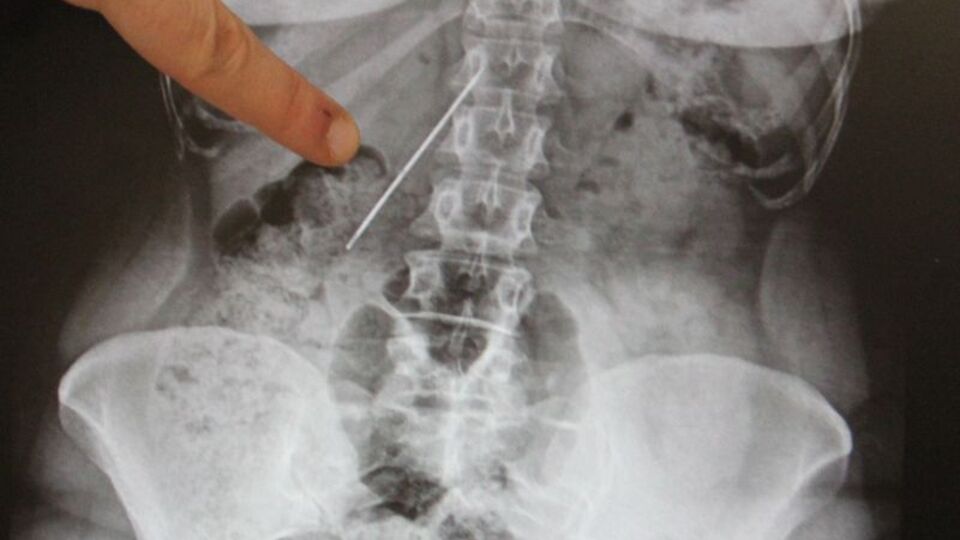

AA'nın haberine göre; doktorlar çekilen filmde hastanın karın bölgesinde 15 santimetre uzunluğunda bir iğne tespit etti. Bir hafta sonra ameliyata alınan Çalışkan'ın vücudundaki iğne yerinden kaydığı için çıkarılamadı. Başarısız geçen operasyonun ardından çekilen filmde, iğnenin hastanın sağ böbrek ile kalın ve ince bağırsağa yakın yerde olması nedeniyle yeni bir operasyon yapılamadı.

İğnenin zamanla hastanın yaşam kalitesini etkilediğini ifade eden Arazi, "Bu iğne çok tehlikeli bir yerdeydi. Sağ böbreğe yakın bir yerle, ince ve kalın bağırsak arasında duruyordu. Ameliyattan önce 15 santimetre uzunluğundaki iğneyi çıkarmak için bir planlama yaptık. Diğer organlara zarar vermeden bir saat süren operasyonun ardından çıkarmayı başardık" diye konuştu.